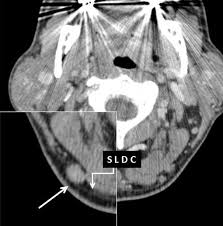

In case of occipital lymph nodes, the most likely culprit in cancer is a squamous cell carcinoma of the scalp. In this case report, we describe an npc patient with occipital lymph node metastasis. They ultimately drain into the deep lymph nodes. 50% off with $15/month membership. Had a neck injury for a month from going to the gym, noticed the lump when massaging the area, neck pain has now gone but lump still there. Had enlarged occipital lymph node on the right side of my neck for the past 4 to 5 week. Swollen cervical nodes are rarely a sign of cancer. The mass was found in the deep layer of subcutaneous tissue just over the semispinalis muscle, sitting on top of the lesser occipital nerve, which was preserved through delicate dissection using loupe magnification.

In this case report, we describe an npc patient with occipital lymph node metastasis. All humans have from one to three occipital lymph nodes at the back of the head and neck. Had enlarged occipital lymph node on the right side of my neck for the past 4 to 5 week. If you have occipital lymph node swelling, it generally suggests you have an infection in the scalp or in the head. The occipital lymph nodes are 1 to 2 cm oval or ball shaped glands. The system acts as the secondary unit of the body's immune system. The mass was found in the deep layer of subcutaneous tissue just over the semispinalis muscle, sitting on top of the lesser occipital nerve, which was preserved through delicate dissection using loupe magnification. 50% off with $15/month membership.

All humans have from one to three occipital lymph nodes at the back of the head and neck. The mass was found in the deep layer of subcutaneous tissue just over the semispinalis muscle, sitting on top of the lesser occipital nerve, which was preserved through delicate dissection using loupe magnification. The clinical presentation, diagnostic procedure, treatment, and outcome of this case were presented, with a review of the related literature. Surgeons, radiologists, and pathologists should be vigilant in identifying, removing, and analyzing scalp slns. Contaminants and debris that drain pipes from the scalp can cause an infection and cause your occipital lymph nodes to swell. But as a result of the inflammatory process, there is an increase in the occipital lymph nodes, as a result of which small rounded tubercles appear on the neck, which, when palpated, can become very painful. The occipital lymph nodes are in the back of the neck. The occipital lymph nodes, one to three in number, are located on the back of the head close to the margin of the trapezius and resting on the insertion of the semispinalis capitis. They are located near the occipital bone of the skull, just outside of the skull, on the back of your head. Doctors refer to nodes in this area as occipital lymph nodes. Occipital lymph nodes are lymph nodes found at the back of the head and near the skull's occipital bone. These systems, in combination, fight the various disease causing pathogens like viruses and bacteria. They ultimately drain into the deep lymph nodes.

If you have occipital lymph node swelling, it generally suggests you have an infection in the scalp or in the head. Lymph nodes in its normal stage indicate the proper health, but at its swollen stage, it just indicates the inflectional influence or illness. The bone behind your skull is called the occipital bone, and there are nodes near this bone, which is why they are called the occipital lymph nodes. The occipital lymph nodes at the top of your neck can also swell if you have a viral or bacterial infection. Had enlarged occipital lymph node on the right side of my neck for the past 4 to 5 week. The mass was found in the deep layer of subcutaneous tissue just over the semispinalis muscle, sitting on top of the lesser occipital nerve, which was preserved through delicate dissection using loupe magnification. Histopathological findings of the mass reported benign, reactive hyperplasia of the lymph node. These nodes are present at the back portion of the head.